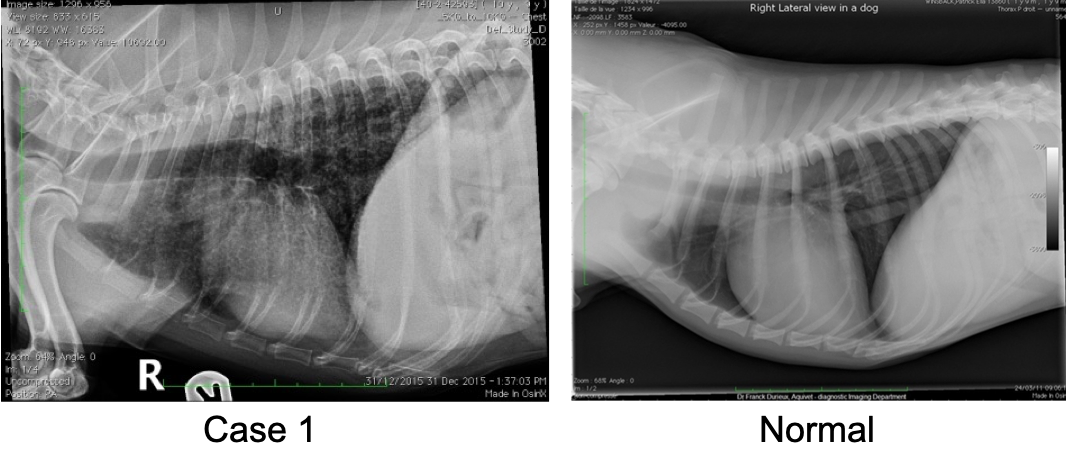

Q

What finding is shown on these radiographs?

A

A single mass (pulmonary neoplasia)